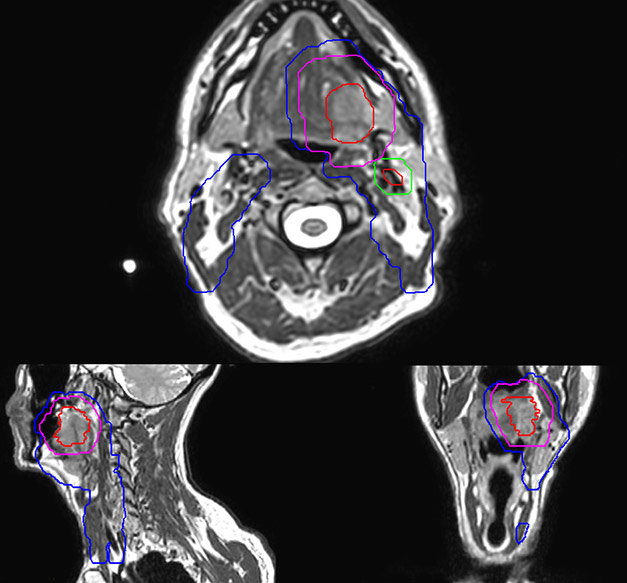

Personalized VMAT dose planned in Philips Pinnacle.